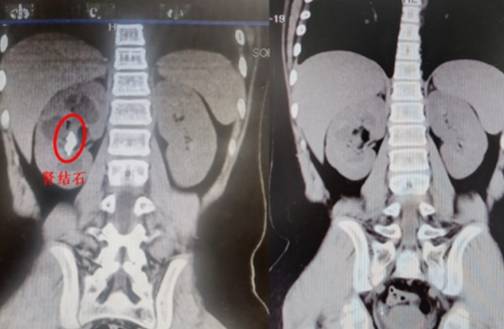

— 超微通道、完全无管化 湘雅专家为患儿清除肾脏结石 —